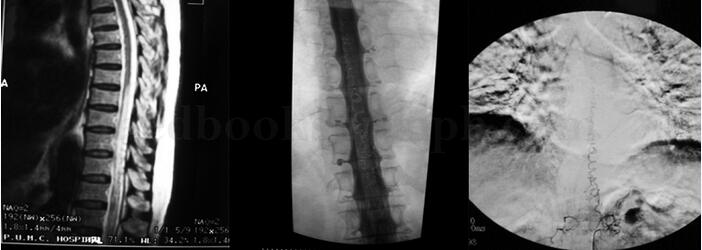

1小时条评论女性,76岁,右利手。 主诉:双下肢无力3年余,麻木10个月,加重伴疼痛2个月。 病史:患者于2001年因血压不稳在外院住院期间逐渐出现双下肢无力,站立不稳,仅可扶墙行走约十几米,不伴有感觉异常和尿便障碍。按膝关节骨质增生进行左膝关节腔内注射治疗无效,双下...